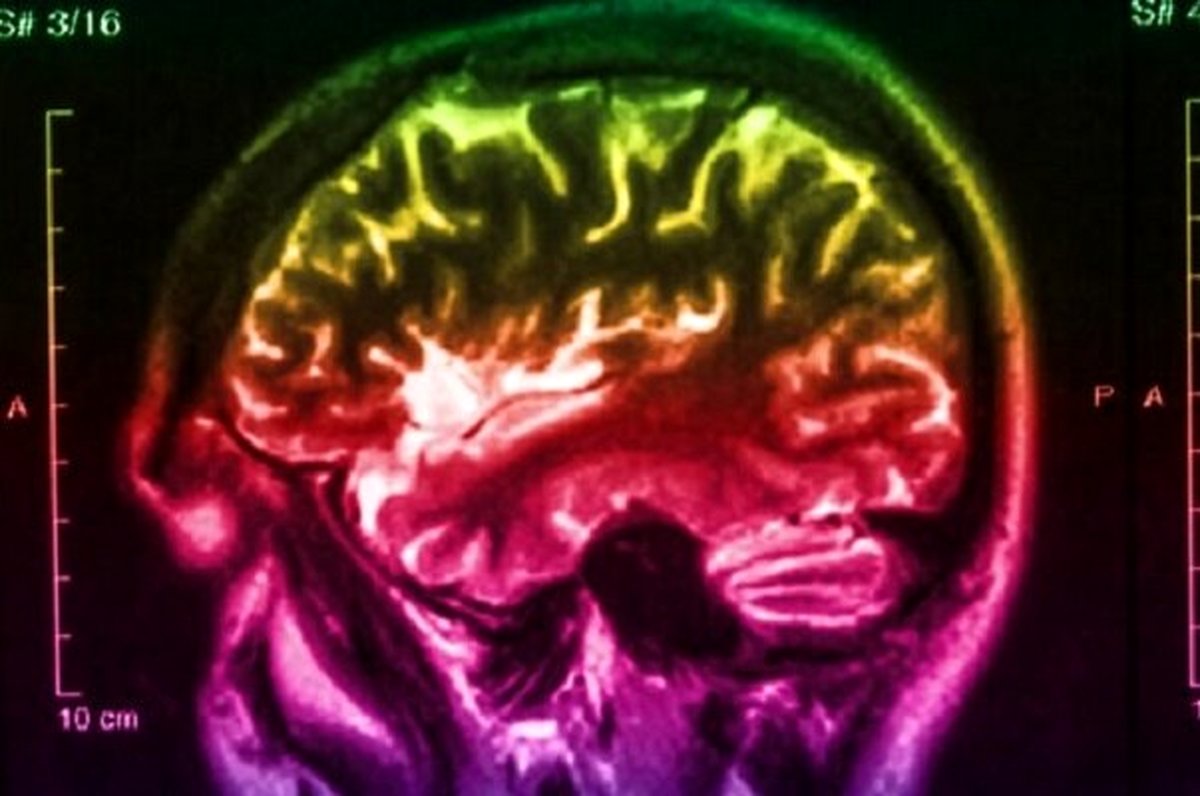

تحقیقات محققان کالج کینگ لندن نشان داده که در اولین مراحل شکل گیری بیماری پارکینسون تغییراتی در سیستم سروتونین مغز صورت می گیرد که بعد از حدود 20 سال به وخیم شدن شرایط بیمار و ابتلای وی به پارکینسون می انجامد. همین کشف موجب طراحی یک سیستم جدید تصویربرداری از مغز برای تشخیص این بیماری شد.

محققان برای تکمیل سیستم تصویربرداری یادشده حدود دو سال وقت صرف کرده اند و 14 نفر از این طریق مورد تصویربرداری قرار گرفته اند تا تغییرات سیستم عصبی آنها به علت تحولات سیستم سروتونین مغز مشخص شود. آنها می گویند این تحولات یک شاخص قابل اعتماد برای پیش بینی ابتلای افراد به پارکینسون طی دو دهه آینده است. البته سیستم اسکن مغزی که بدین منظور به کار می رود فعلاً پرهزینه است و محققان درصدد یافتن راهی برای کاهش هزینه این کار هستند.